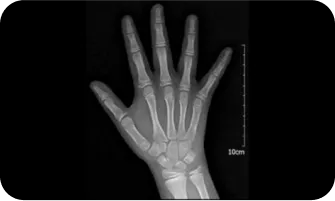

02

엑스레이 검사를 이용한

여아의 골연령검사

300점

400점

8.5세

500점

10세

600점

11세

700점

12세

800점

13 ~ 14세

900점

14 ~ 15세

1000점

15세 ~